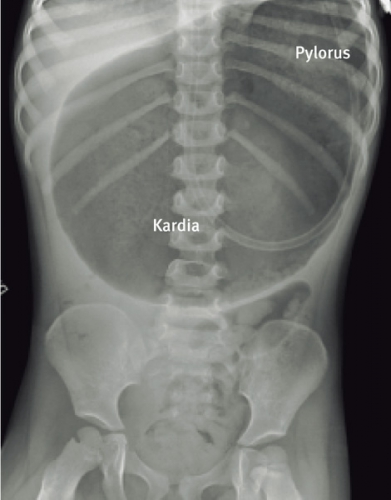

Buköversikt visar en distenderad ventrikel liggande i det vertikala planet (mesenteroaxial) (Figur 2) eller i det horisontella planet (organoaxial) (Figur 3). En kraftigt dilaterad ventrikel kan försvåra diagnosen, eftersom det kan vara svårt att definiera ventrikelns olika delar. Avlastning med ventrikelsond och därefter övre passageröntgen ger diagnosen.

Vid mesenteroaxial volvulus är ventrikeln uppochnervänd, med pylorus ovanför den gastroesofageala övergången (kardia) (Figur 4). Vid organoaxial volvulus är ventrikeln liggande i horisontalplanet, med curvatura major ovanför curvatura minor (Figur 5).